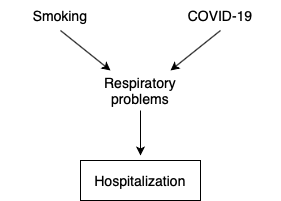

A Tour of Causal Inference

Thy Nguyen ’21 (Hanoi, Vietnam),

Applied mathematics & statistics

-

“Correlation is not causation”. Well then, what is? What are the conditions that must be met before a claim can be made about the relationship between two variables? When can we say that one causes the other? And if so, to what extent? Most importantly, why do we need to be so careful when throwing the words “cause” and “causal” around? In this research project, I attempt to provide an overview of causal inference, or the study of cause-and-effect relationships, and investigate a link between smoking and COVID-19 to demonstrate why the field is so important.